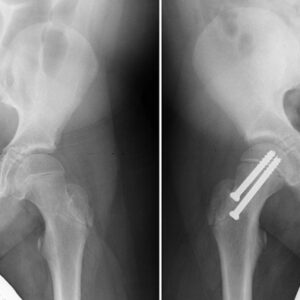

Hip Patient informationOverview Meta Description: Explore an in-depth scientific overview of Developmental Dysplasia of the Hip (DDH), its causes, risk factors, diagnosis, treatment, and long-term outcomes. SEO Keywords: developmental dysplasia of the hip, DDH, congenital hip dislocation, infant hip dysplasia, Pavlik harness, hip surgery, orthopaedics, musculoskeletal disorders Introduction Developmental Dysplasia of the